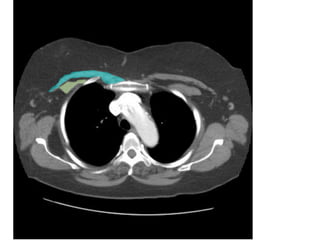

VỠ LOÉT ĐỘNG MẠCH CHỦ NGỰC

-> MÁU XOANG NGỰC (T)